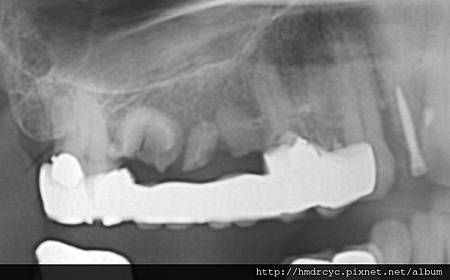

在牙橋有時感覺動搖度並不大

那是因為跟其他牙齒聯結在一起的關係

單顆牙齒骨頭破壞嚴重就會馬上出現動搖

骨頭破壞後原本骨頭位置被發炎的肉取代

甚至形成膿包

根管化膿是原本神經管裡的組織感染

因為上面有牙套 所以就往牙根尖方向蔓延

這會發生在沒有先做根管治療的牙齒

以及根管治療不完全的牙齒

解決方案必須考慮牙套拆除

重新根管治療 甚至牙根尖手術去除膿包

不然有時膿包繼續擴大

會感染到隔壁牙齒甚至形成囊腫